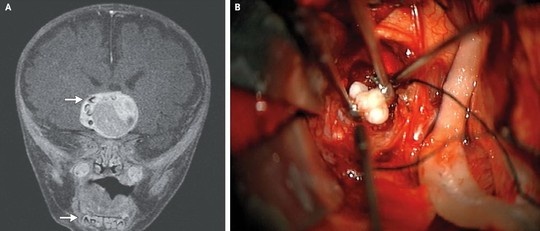

| Chiếc răng trong khối u não của bé trai 4 tháng tuổi. |

Bác sĩ Beaty nói: “U sọ hầu thường chứa chất lắng đọng can-xi nhưng việc lấy ra chiếc răng đầy đủ như trường hợp này là cá biệt”.